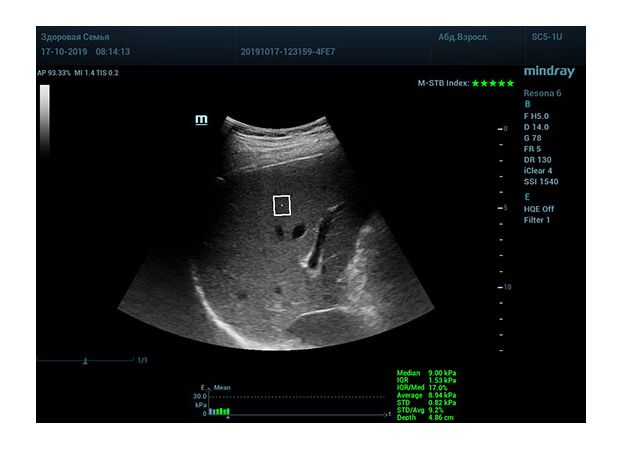

Определение плотности печени. Не ошибся ли оператор при измерении эластических свойств печени? Для оценки критериев качества предусмотрен индекс MBT, который покажет насколько «твердой» была рука оператора и двигалась ли печень. При MBT 5* рука тверда и показатели достоверны. Для оценки качества результатов используется IQR индекс, отображающий колебания показателей в точке измерения при расчете медианы. Показатели при IQR <30% считаются приемлемыми. Техника сканирования через межреберные промежутки требует размещение окна интереса на несколько сантиметром ниже капсулы, для исключения эффекта реверберации. Установка ROI на паренхиму без захвата сосудов, для исключения погрешностей измерения.